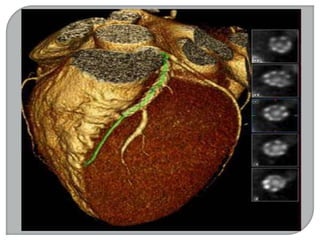

RESSONÂNCIA MAGNÉTICA

RESSONÂNCIA MAGNÉTICA NUCLEAR

RM, RMN, IRM.

Em 1977 Damadian e sua equipe produziram

com sucesso o primeiro aparelho de RM, do

corpo humano